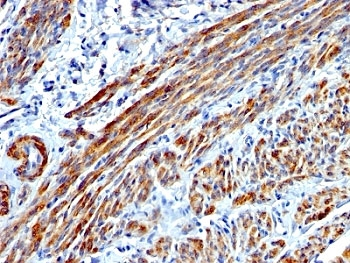

IHC: Formalin-fixed, paraffin-embedded human Leiomyosarcoma stained with SMMHC antibody (MYH11/923).